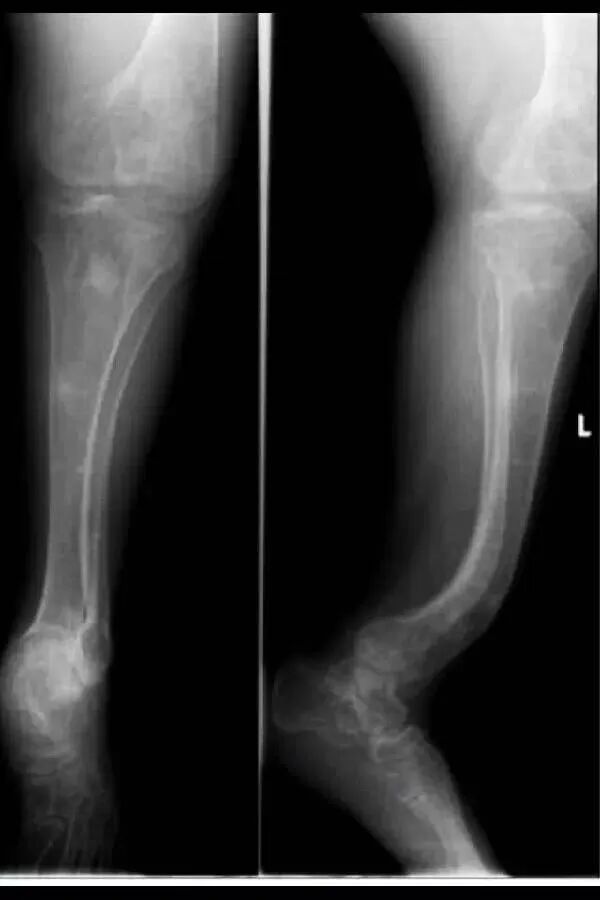

OI标志性特征是骨质脆弱反复骨折, 典型骨骼X线表现(见图二);成骨不全症的临床表现不仅限于骨骼,还常常累及其他结缔组织如眼、耳、皮肤、牙齿等(见图三)。根据临床表型, 澳洲悉尼大学的Sillence教授将OI 分成至Ⅰ-Ⅳ型[7]: Ⅰ型病情最轻, 最常见; Ⅱ最重, 通常围产期致死; Ⅲ型是存活者中最严重的, 常常身材矮小, 呈进行性骨骼畸形; Ⅳ型严重度介于Ⅰ型与Ⅲ型之间。近期发现的Ⅴ型OI 具有肥厚性骨痂、桡骨头脱位、前臂骨间膜钙化、桡骨干骺端下密集骺线等独特临床表现(见图四)。

a.股骨干侧位片显示双侧非对称的股骨前弓弯曲愈合中的骨折(实心箭头)和已经愈合的骨折(空心箭头)

b. 胫骨侧位片显示双侧胫骨向前弯曲以及骨折愈合的不同阶段:早期愈合(实心箭头),进行性愈合中(空心箭头),已经愈合(三角);双侧胫骨呈现铅笔样畸形,尤其是腓骨及蜂巢状髓腔,特别是胫骨远端。